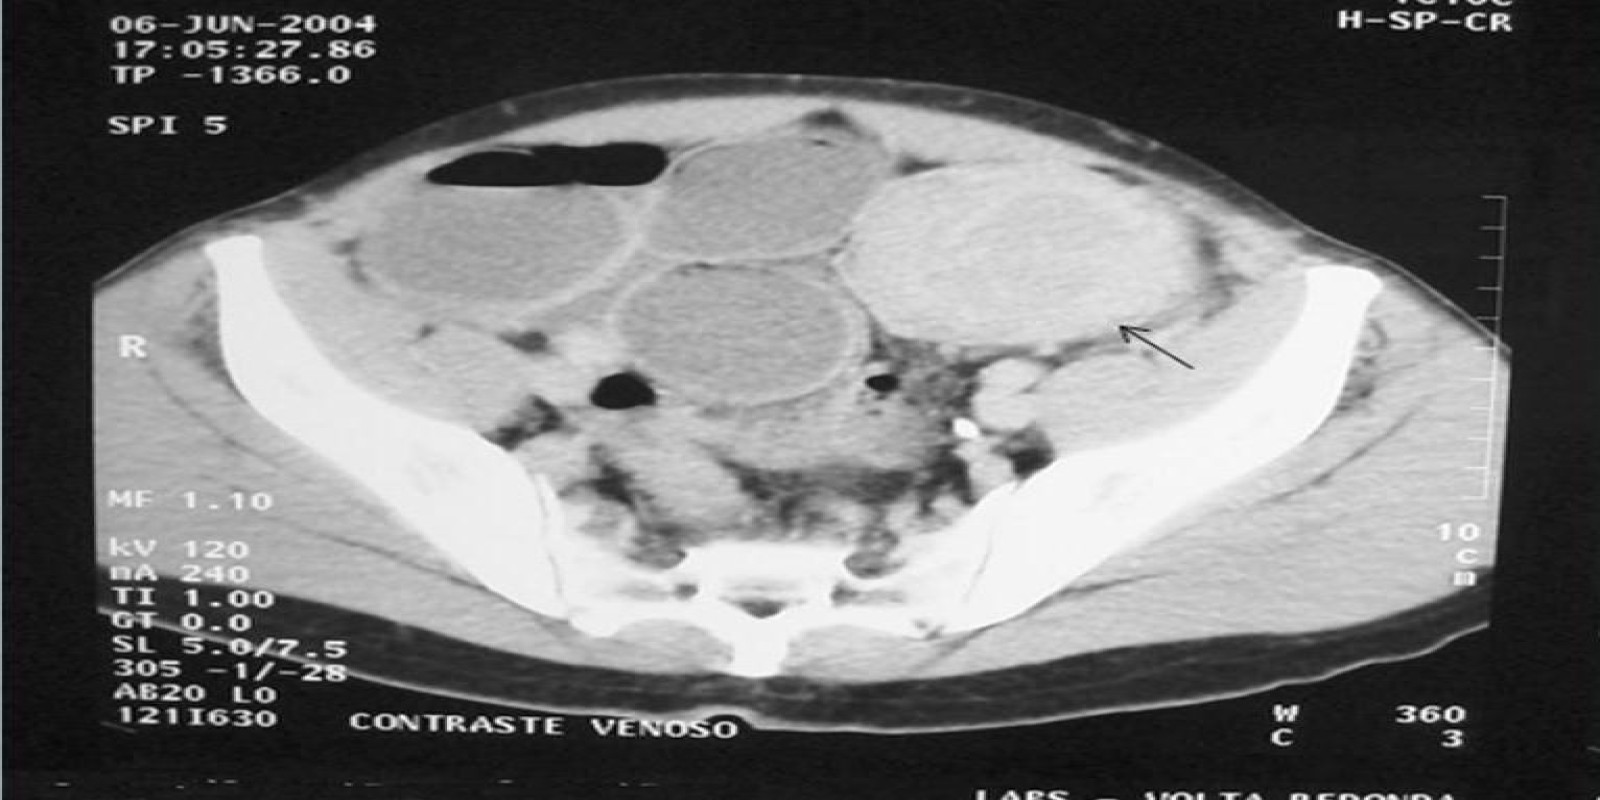

Caso Código 277A de Obstrução Intestinal do Cólon

Cod.: 277A